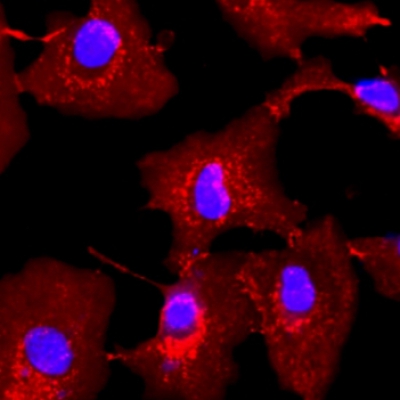

细胞/分子/ 电镜